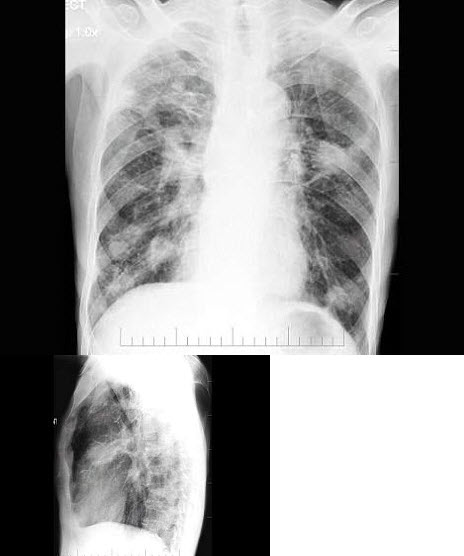

22、单项选择题

女,51岁,胸闷、咳嗽、咳痰2月余,3年前被确诊为子宫平滑肌肉瘤,结合胸片,最可能的诊断是()